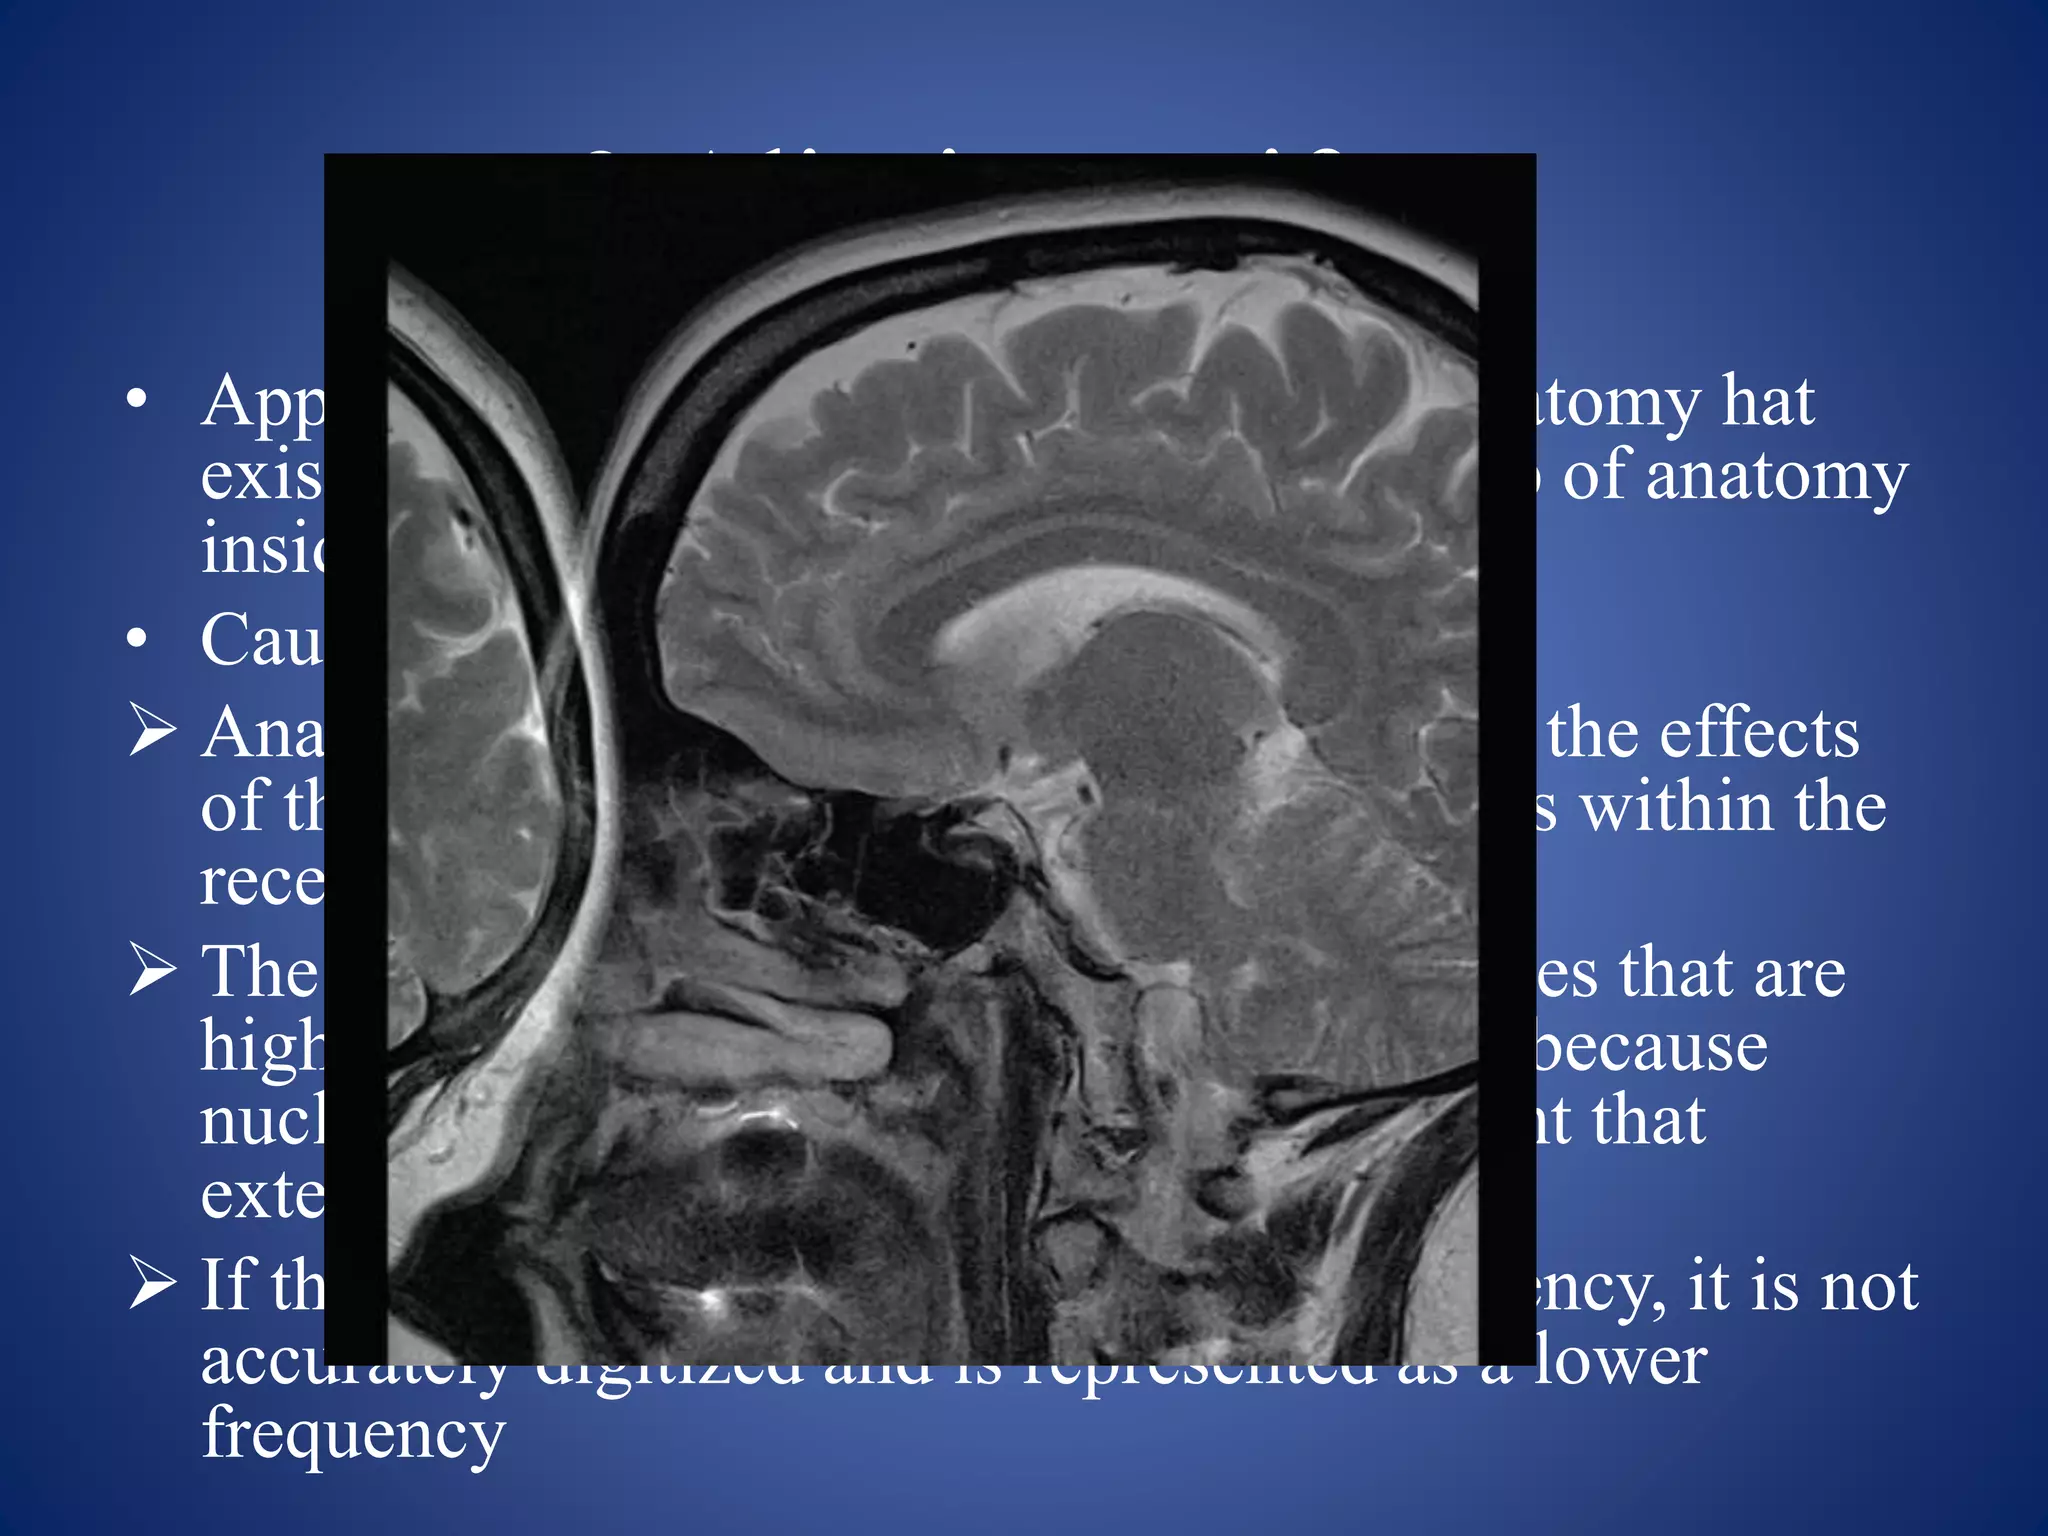

• Appearance: appears as the wrap where anatomy hat

exist outside the FOV is folded onto the top of anatomy

inside FOV

• Causes:

 Anatomy outside the FOV still experiences the effects

of the gradients and produces a signal if it is within the

receiving volume of the receiver coil.

 The signal from this anatomy has frequencies that are

higher or lower than those within the FOV because

nuclei are positioned on parts of the gradient that

extend beyond the FOV.

 If the frequency exceeds the Nyquist frequency, it is not

accurately digitized and is represented as a lower

frequency